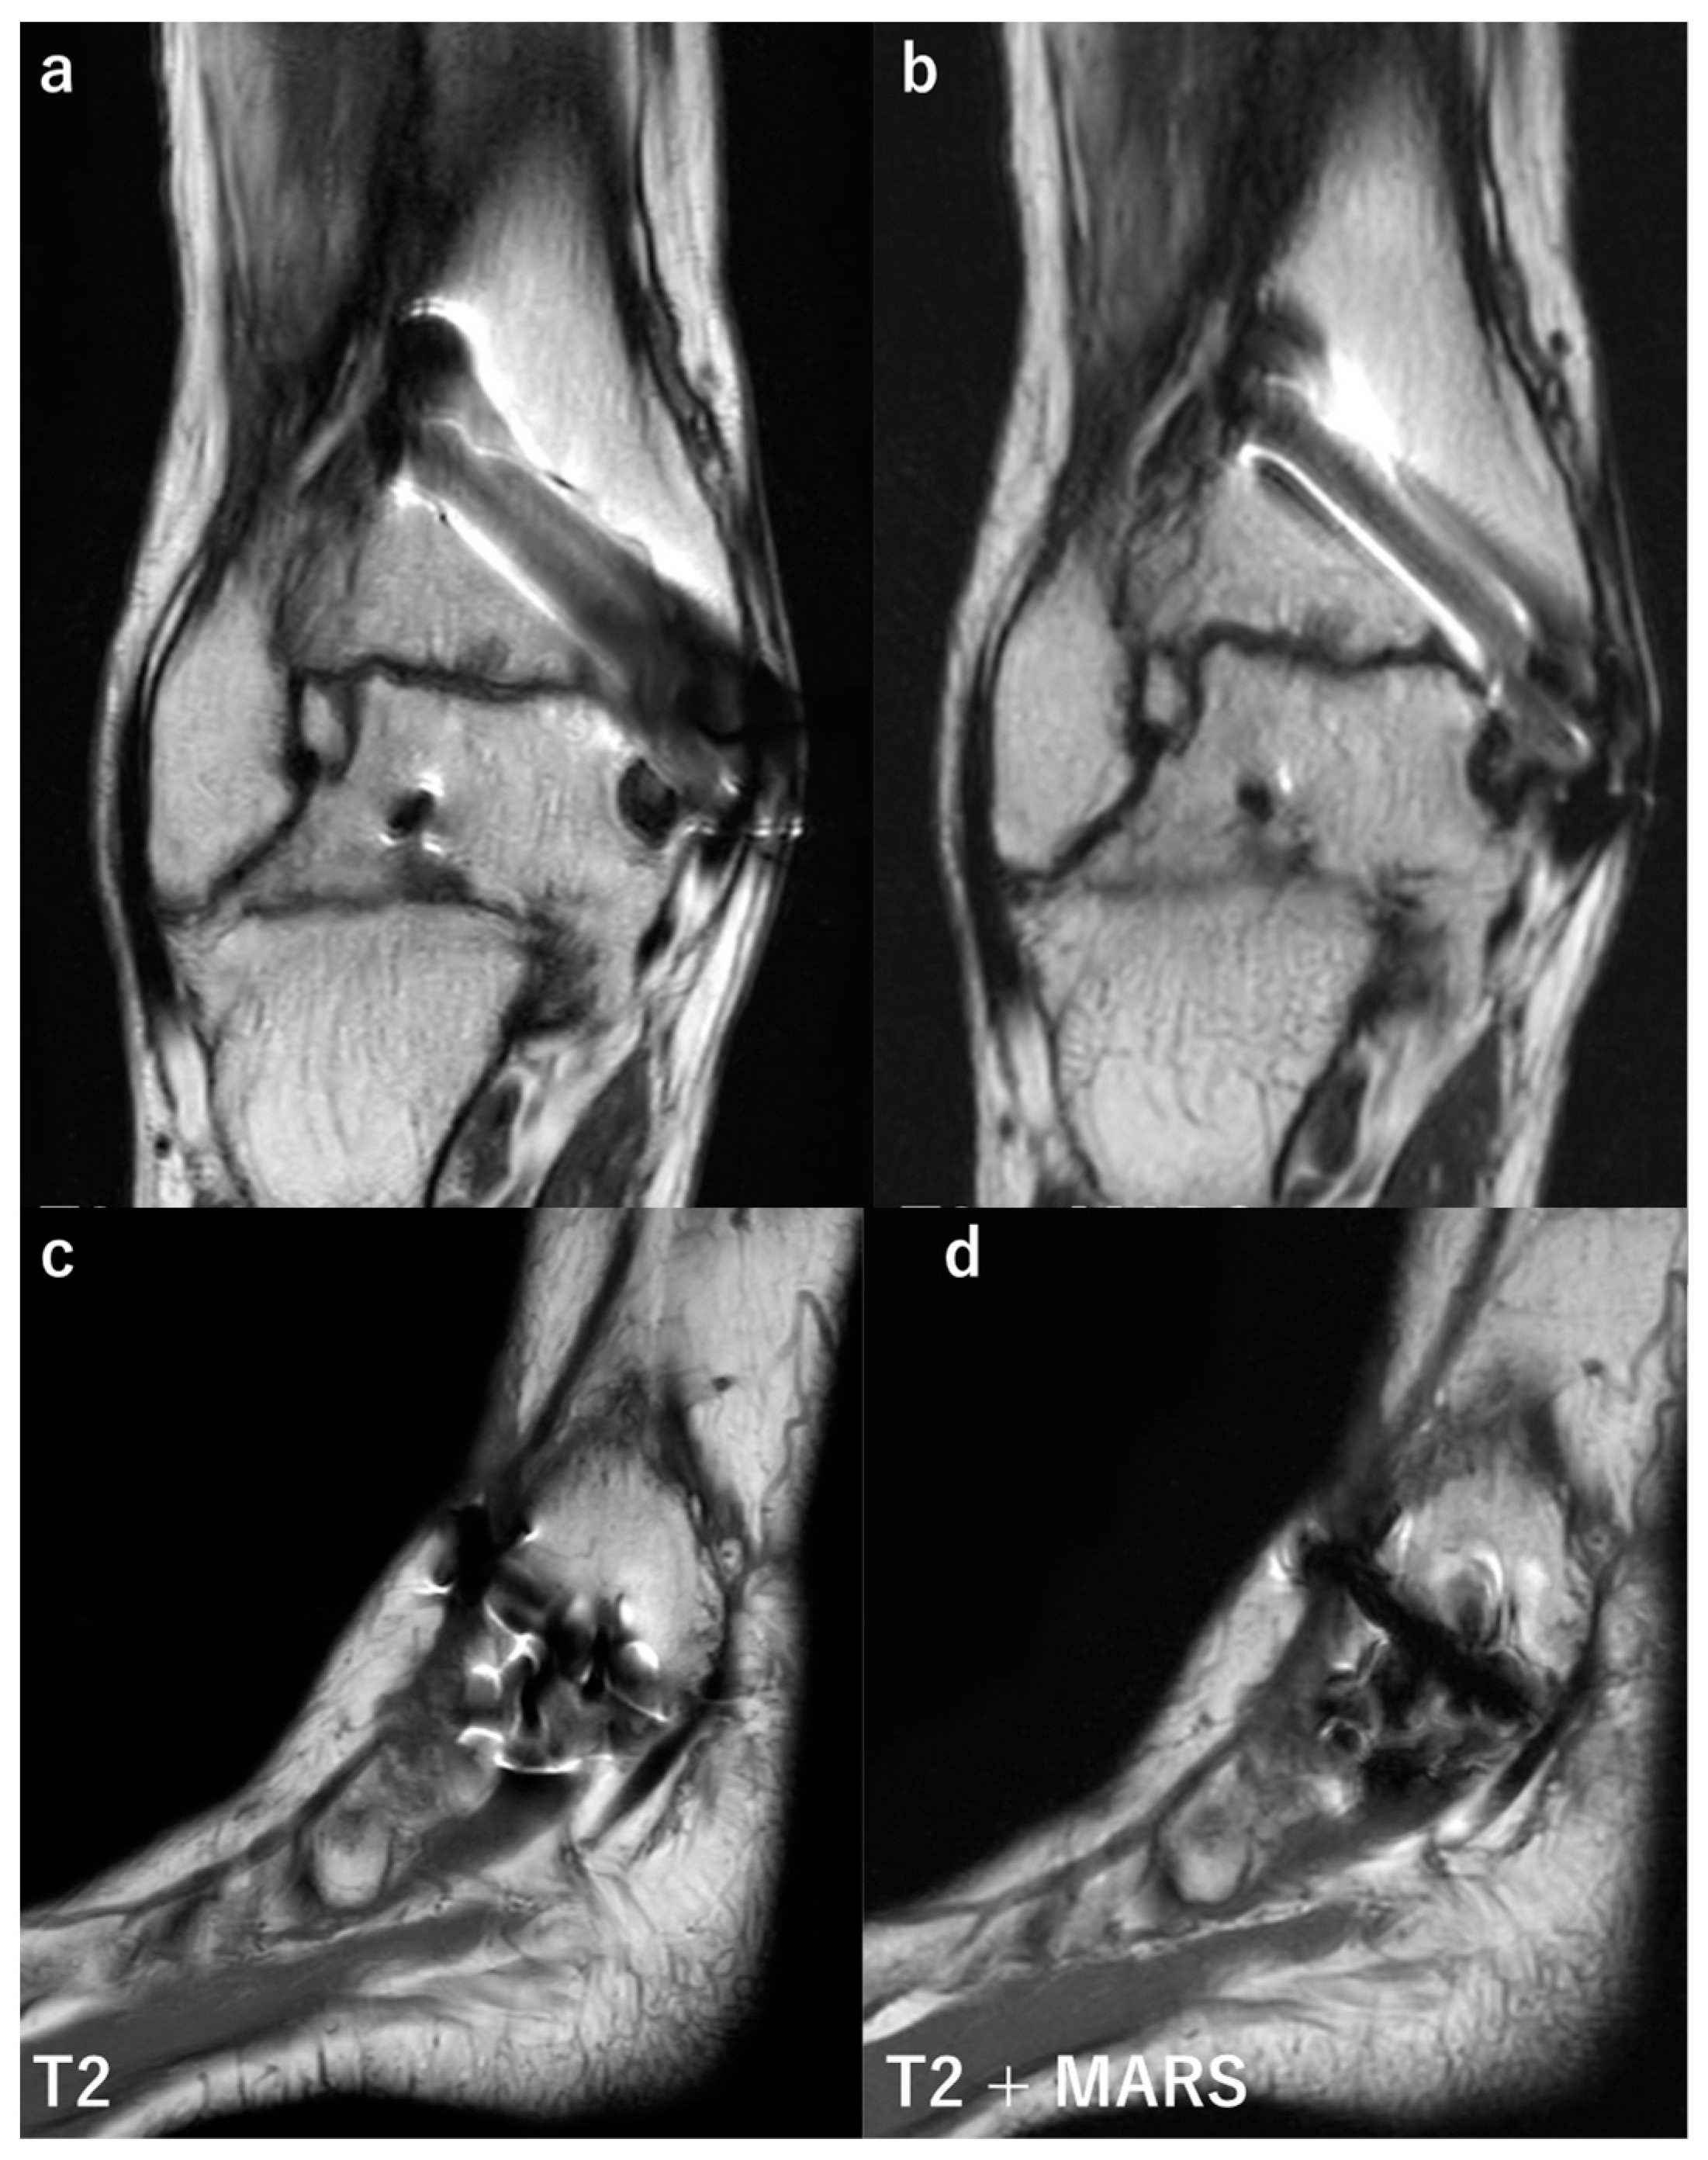

- Sutter, R.; Hodek, R.; Fucentese, S.F.; Nittka, M.; Pfirrmann, C.W.A. Total Knee Arthroplasty MRI Featuring Slice-Encoding for Metal Artifact Correction: Reduction of Artifacts for STIR and Proton Density–Weighted Sequences. Am. J. Roentgenol. 2013, 201, 1315–1324. [Google Scholar] [CrossRef]

- Fritz, J.; Ahlawat, S.; Demehri, S.; Thawait, G.K.; Raithel, E.; Gilson, W.D.; Nittka, M. Compressed Sensing SEMAC: 8-fold Accelerated High Resolution Metal Artifact Reduction MRI of Cobalt-Chromium Knee Arthroplasty Implants. Investig. Radiol. 2016, 51, 666–676. [Google Scholar] [CrossRef]

- Netto, C.D.C.; Fonseca, L.F.; Fritz, B.; Stern, S.E.; Raithel, E.; Nittka, M.; Schon, L.C.; Fritz, J. Metal artifact reduction MRI of total ankle arthroplasty implants. Eur. Radiol. 2018, 28, 2216–2227. [Google Scholar] [CrossRef] [PubMed]